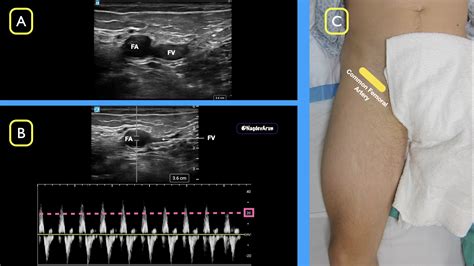

Understanding the Femoral Artery Pulse is crucial for healthcare professionals and individuals interested in monitoring cardiovascular health. The femoral artery, located in the groin area, is a major blood vessel that supplies oxygenated blood to the lower extremities. Checking the femoral artery pulse can provide valuable insights into a person's overall cardiovascular status and help detect potential issues early.

The femoral artery is the largest artery in the thigh and is a continuation of the external iliac artery. It begins just below the inguinal ligament and runs down the thigh, eventually becoming the popliteal artery behind the knee. The femoral artery is easily accessible for pulse checks and other diagnostic procedures, making it a vital point for assessing blood flow and cardiovascular health.